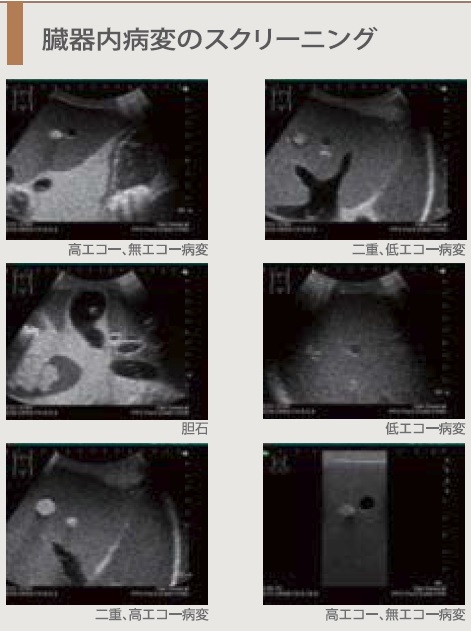

商品詳細|11481|GEヘルスケアジャパン|超音波診断装置|Vivid, 超音波検査 - 画像部門(放射線) - 診療科・部門案内 | 大垣,

超音波検査 - 画像部門(放射線) - 診療科・部門案内 | 大垣, 商品詳細|11481|GEヘルスケアジャパン|超音波診断装置|Vivid,

商品詳細|11481|GEヘルスケアジャパン|超音波診断装置|Vivid, 楽天市場】腹部エコー 超の通販,